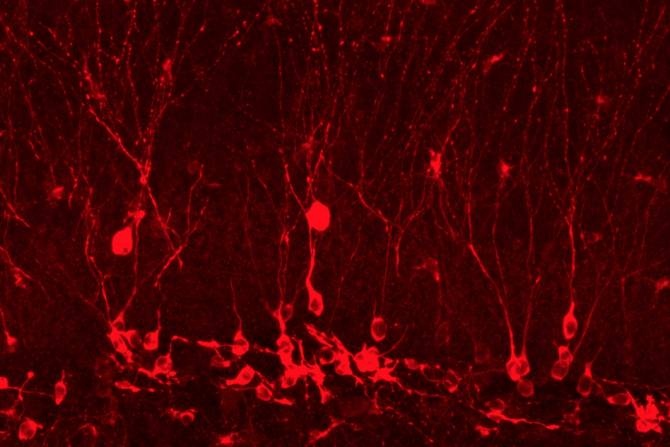

Así lo ha demostrado el equipo de Susumu Tonegawa y Steve Ramirez, del Instituto Tecnológico de Massachusetts (MIT), en Cambridge, Estados Unidos. En sus experimentos con ratones, los investigadores encontraron que permitirles a los ratones llevar a cabo experiencias agradables después de deprimirse no mejoraba sus síntomas tanto como reactivar en ellos un recuerdo agradable antiguo. Era pues el efecto de rememorar los viejos recuerdos lo que ejercía la influencia beneficiosa, que se tradujo incluso en la formación de nuevas células cerebrales.

Los resultados de esta investigación ofrecen una posible explicación para el éxito de las psicoterapias en las que los pacientes de depresión son animados a recordar experiencias agradables. Lo descubierto en el nuevo estudio sugiere también nuevas formas de tratar la depresión mediante la manipulación de las células cerebrales donde están almacenados los recuerdos. Los investigadores creen que este enfoque selectivo y de precisión sobre puntos muy específicos del cerebro podría tener menos efectos secundarios que la mayoría de fármacos antidepresivos, que bañan a todo el cerebro.

Una vez se identifiquen con la debida certeza todos los lugares específicos en el circuito de recuerdos que no están funcionando bien, o cuya potenciación traerá consecuencias beneficiosas, se abrirá para los pacientes la posibilidad de que el desarrollo de nuevas tecnologías médicas permita inducir mejoras en partes muy concretas del circuito cerebral, un planteamiento más prometedor que la estrategia típica seguida hoy en día con el uso de fármacos cerebrales: administrar el producto y dejar que este actúe en todas partes del cerebro.